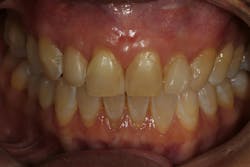

Its application has garnered attention for restoring esthetics and improving oral health among patients with mild to moderate gingival recession in multiple sites.3,4 Recent studies have shown that the PST technique is comparable to the gold standard of soft-tissue grafting, which involves harvesting connective tissue from the palate or other areas of the patient’s mouth.1,2

Multiple studies have highlighted the efficacy of PST in reducing gingival recession in both length and width. PST has also shown a remarkable ability to stabilize keratinized tissue width (KTW), enhance gingival thickness (GT), and achieve complete root coverage (CRC). These outcomes are particularly valuable for individuals with MAR where simultaneous multisite treatment is essential for uniformity and esthetics. The PST technique has demonstrated good long-term stability in treating soft-tissue recession and is similar to soft-tissue grafting with the patient’s own connective tissue.2

- Long-term esthetic and clinical outcomes. The ability of PST + PRF to maintain long-term outcomes is another advantage. Studies have demonstrated that patients undergoing this combined therapy exhibit not only durable improvements in gingival health but also a higher level of satisfaction with root-coverage esthetics when compared to PST alone.6